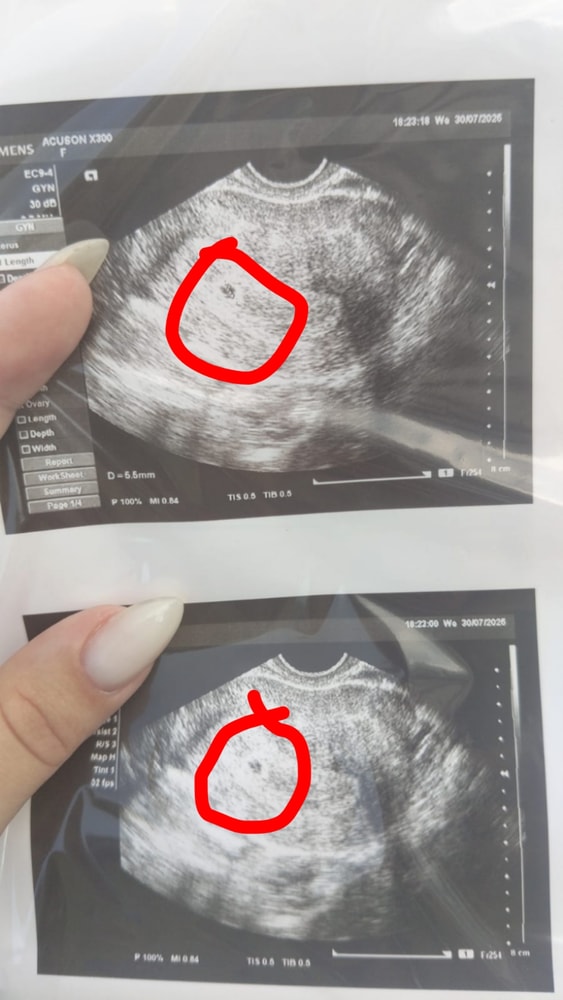

Узи 5 недель акушерских

Анализы, скринингиСегодня увидели пя 5 недель акушерских, 3 эмбриональных 😊💞

У нас сроки почти одинаковые последние м 25.06, овуляция 8 июля. Тоже на 5 нед сходила увидели пя 4,5 мм